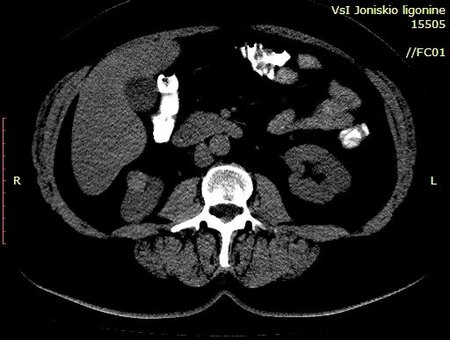

Женщина 55 лет, жалоб нет.

В нижнем полюсе правой почки обнаружено такое образование.

Выполнена КТ с контрастированием.